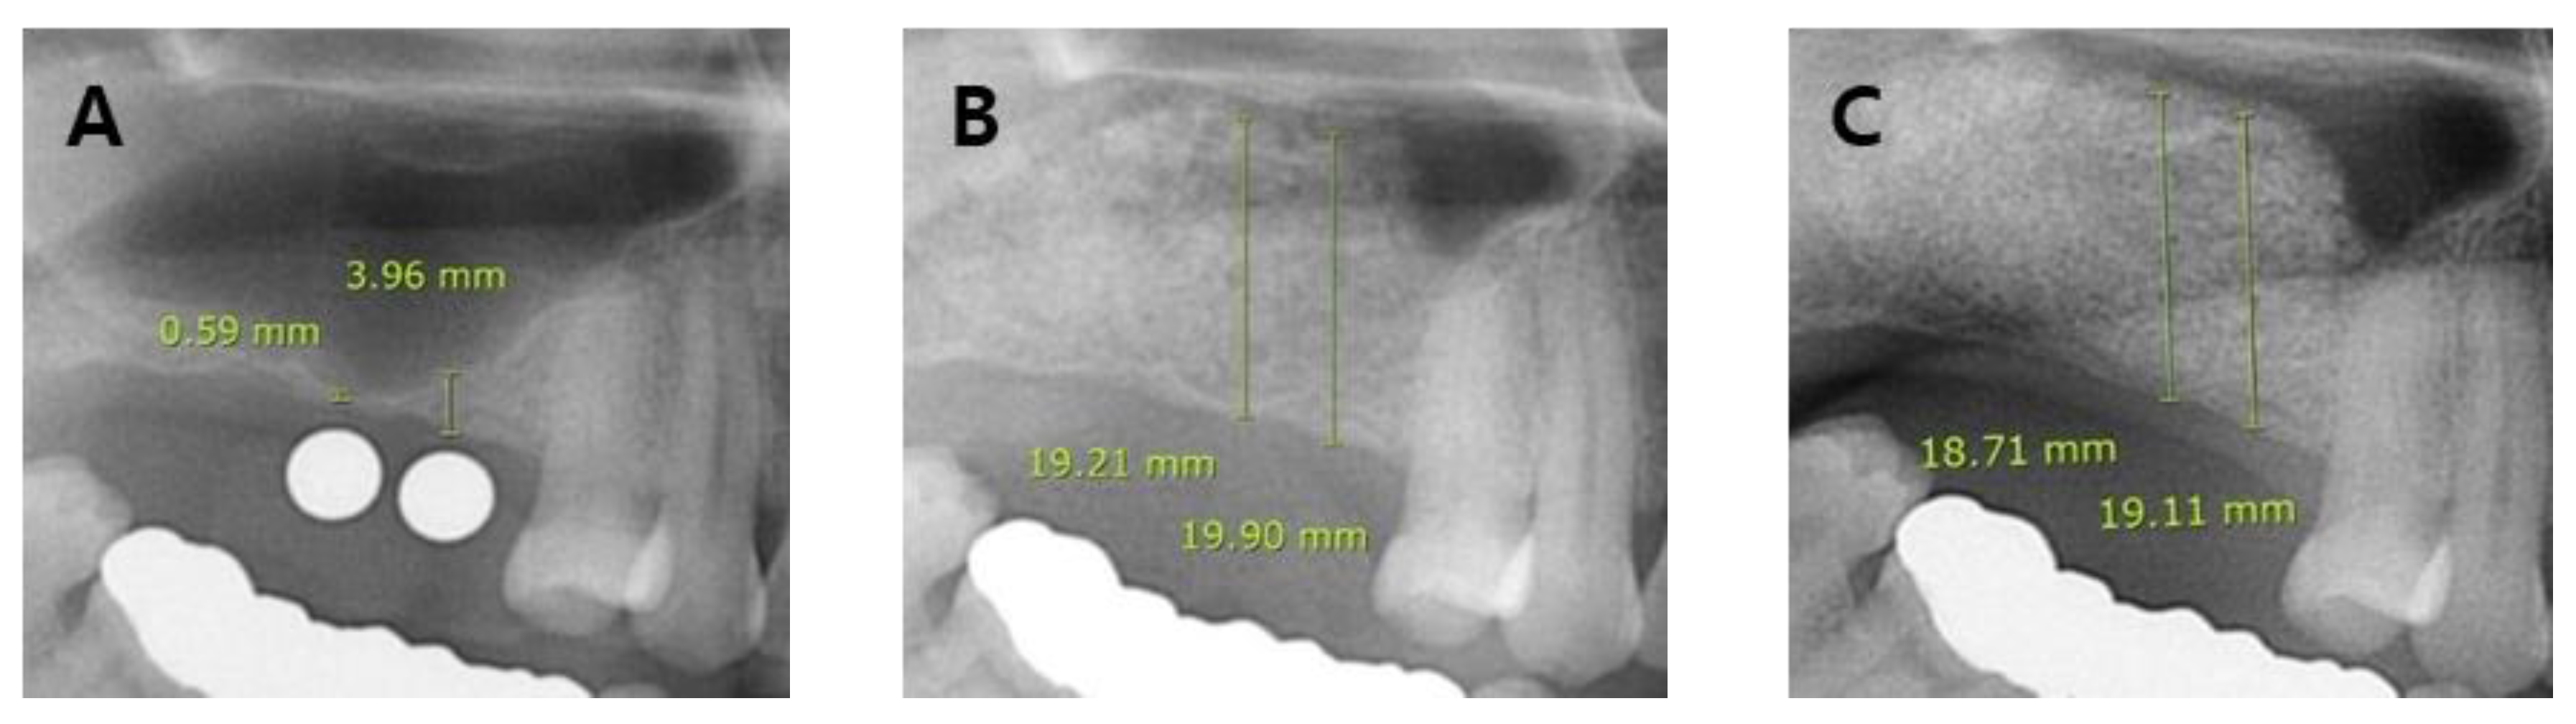

- (A)

- Group 1: No SMP but the membrane was weakened (or thinned) during sinus lift procedure;

- (B)

- Group 2: SMP was small to medium in size (< 10 mm) during sinus lift procedure;

- (C)

- Group 3: SMP was large in size (> 10 mm) during sinus lift procedure;